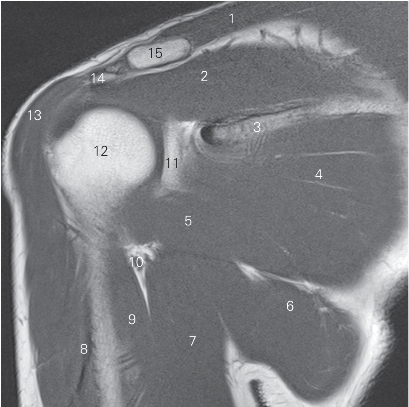

图4-21 经肩锁关节的矢状断层MR T2WI FS

1 锁骨 clavicle 2 肩锁关节 acromioclavicular joint

3 肩峰 acromion 4 冈下肌 infraspinatus

5 肱骨头 head of humerus 6 三角肌 deltoid

7 小圆肌 teres minor

8 腋神经及旋肱后动脉 axillary nerve and posterior humeral circumflex artery

9 肱三头肌 triceps brachii 10 大圆肌 teres major

11 胸大肌 pectoralis major 12 喙肱肌 coracobrachialis

13 肩胛下肌 subscapularis 14 喙突 coracoid process

15 肩袖间隙 rotator interval 16 冈上肌 supraspinatus

17 喙肩韧带 coracoacromial ligament